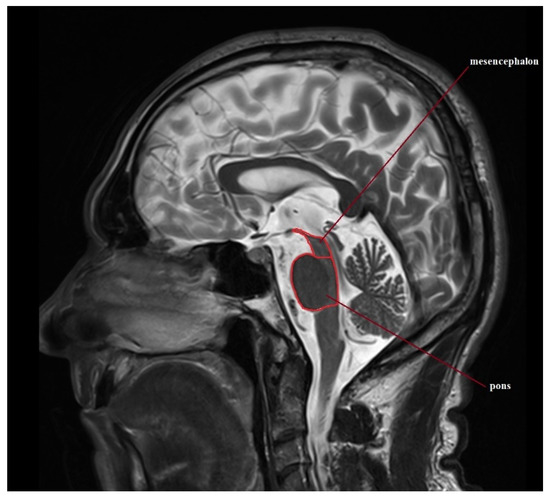

| PONS (cm2) | 4.96 (3.6–6.6) | 0.73 ± 0.54–1.13 | 4.79 (3.75–5.79) | 0.61 ± 0.44–1.01 | 4.77 (4.08–5.55) | 0.39 ± 0.29–0.58 | 4.59 (2.92–5.55) | 0.65 ± 0.5–0.94 | 4.44 (3.32–5.54) | 0.61 ± 0.46–0.9 |

| MIDBRAIN (cm2) | 1.21 (0.7–1.5) | 0.23 ± 0.17–0.35 | 0.76 (0.57–1.03) | 0.12 ± 0.09–0.21 | 0.76 (0.42–1.66) | 0.32 ± 0.24–0.47 | 1.08 (0.76–1.5) | 0.19 ± 0.14–0.27 | 0.81 (0.4–1.27) | 0.22 ± 0.17–0.32 |

| M/P ratio | 0.245 (0.194–0.313) | 0.034 ± 0.025–0.053 | 0.16 (0.133–0.202) | 0.02 ± 0.014–0.033 | 0.157 (0.098–0.321) | 0.056 ± 0.042–0.083 | 0.239 (0.16–0.344) | 0.054 ± 0.041–0.078 | 0.183 (0.103–0.343) | 0.053 ± 0.04–0.079 |

| MRPI | 11.247 (7.758–15.429) | 1.882 ± 1.39–2.912 | 17.384 (12.025–26.626) | 4.439 ± 3.183–7.327 | 19.366 (9.343–31.303) | 6.944 ± 5.247–10.27 | 10.766 (7.163–17.151) | 2.503 ± 1.915–3.614 | 15.363 (6.582–29.025) | 5.03 ± 3.801–7.439 |

| MRPI 2.0 | 2.342 (1.252–3.463) | 0.619 ± 0.457–0.958 | 4.338 (2.526–6.306) | 1.344 ± 0.964–2.219 | 5.646 (2.595–9.838) | 2.324 ± 1.756–3.436 | 2.558 (1.41–4.549) | 0.91 ± 0.696–1.314 | 4.195 (1.953–9.285) | 1.686 ± 1.274–2.493 |